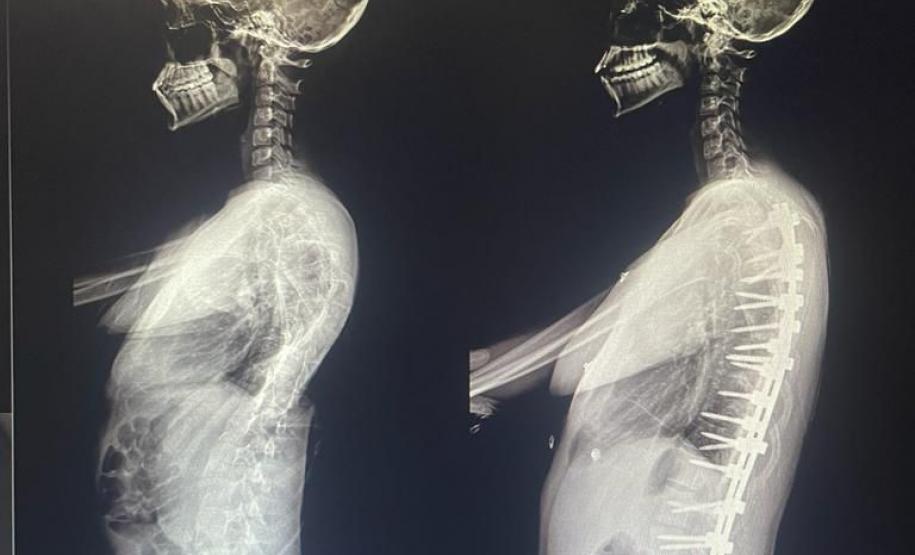

Outro tipo de escoliose é a causada por doenças neuromusculares, como paralisia cerebral, mielomeningocele, distrofia muscular, atrofia muscular espinhal, entre outras. No caso do Lucas Batista da Paixão, de 18 anos, a paralisia cerebral que teve ao nascer foi o que desencadeou a condição.

Com curvatura acima dos 100 graus, desconfortos respiratórios como falta de ar e asma, a posição do adolescente na cadeira de rodas estava bem limitada. Para a mãe de Lucas, Daniele de Oliveira Batista, a cirurgia foi fundamental para melhorar a autonomia e qualidade de vida do filho.

“Foi um longo processo até chegar aqui no CHT, esperávamos por essa cirurgia há mais de dois anos e, depois de tantas dificuldades, hoje conseguimos fazer um passeio sem que ele reclame de dor. Ele também já consegue ficar em muitas outras posições que antes eram desconfortáveis e geravam muita dor. Só temos a agradecer a toda equipe médica pelos cuidados e ótimo atendimento prestado ao meu filho”, disse.